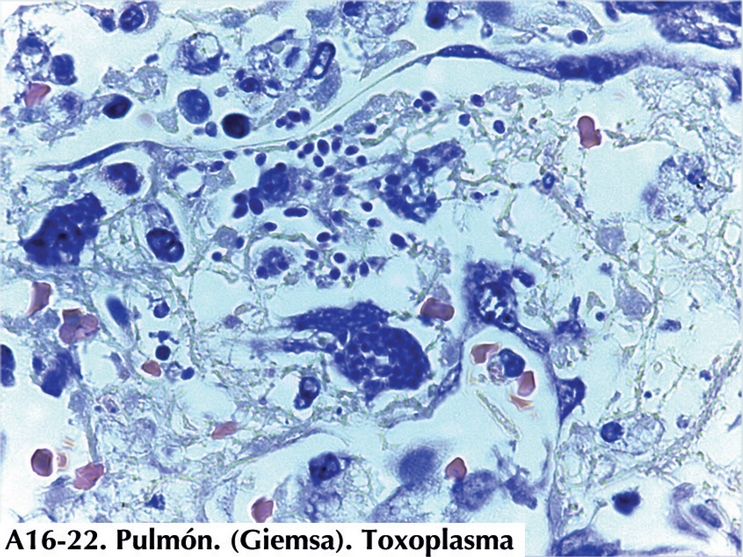

En la autopsia no se encontró linfoma. Lo que más llamó la atención durante la autopsia fue la presencia de frecuentes granulaciones dispersas en los pulmones, de situación subpleural y parenquimatosa. Medían de 2 a 4 milímetros y tenían aspecto de granulomas. Con el microscopio se veía que no eran granulomas sino focos de necrosis, con componentes de daño alveolar agudo, rodeados de alveolos bien ventilados (Figura 8). En el seno de la necrosis, se identificaban numerosos organismos con morfología de Toxoplasma, tanto en forma de pseudoquistes (una célula infectada repleta de taquizoitos) o de taquizoitos dispersos, una vez que la célula infectada ha estallado (Figura 9). Tanto la morfología de los parásitos como el contexto clínico y tisular apoyan fuertemente el diagnóstico de Toxoplasma pero otros microorganismos (Leishmania, Sarcocystis, Besnoitia, Nosema, levaduras ovales y quizás otros) pueden plantear dudas diagnósticas en situaciones especiales. Técnicas de inmunohistoquímica (Figura 10) y de biología molecular que expone más adelante el Dr. Carlos Cedillo aportan una certeza diagnóstica. Pseudoquistes y taquizoitos libres se encontraron en múltiples focos necróticos en médula ósea, en úlceras en estómago y en colon, en focos de necrosis en páncreas y en hígado.

COMENTARIO DE PARASITOLOGÍA Y BIOLOGÍA MOLECULAR (Dr. Cedillo Peláez)

Para la confirmación del diagnóstico anatomopatológico de toxoplasmosis, se llevó a cabo la extracción de DNA a partir de secciones de tejido pulmonar del presente caso, utilizando un estuche comercial (QIAGEN) siguiendo las instrucciones del fabricante con ligeras modificaciones, llevando a cabo la digestión del tejido con proteinasa K, la precipitación del DNA con isopropanol y su purificación con etanol.

Una vez extraído el DNA, se llevó a cabo su diagnóstico molecular utilizando como blanco la región repetitiva de 529 pb, la cual es especifica de T. gondii, realizando un ensayo de PCR punto final. La muestra del caso se corrió a la par con muestras previamente positivas a T. gondii, previamente diagnosticadas con la misma metodología, incluyendo como controles positivos, DNA de las cepas de referencia RH y Me 49, y como control negativo se incluyo una muestra sin DNA, sustituyéndola por agua. Los productos de amplificación obtenidos se visualizaron en un gel de agarosa al 1.5% teñido con bromuro de etidio.

La muestra de tejido pulmonar así como las de los tejidos de referencia resultaron positivas a la amplificación por PCR apreciándose bandas en el peso esperado similares a los controles positivos (Figura 12).